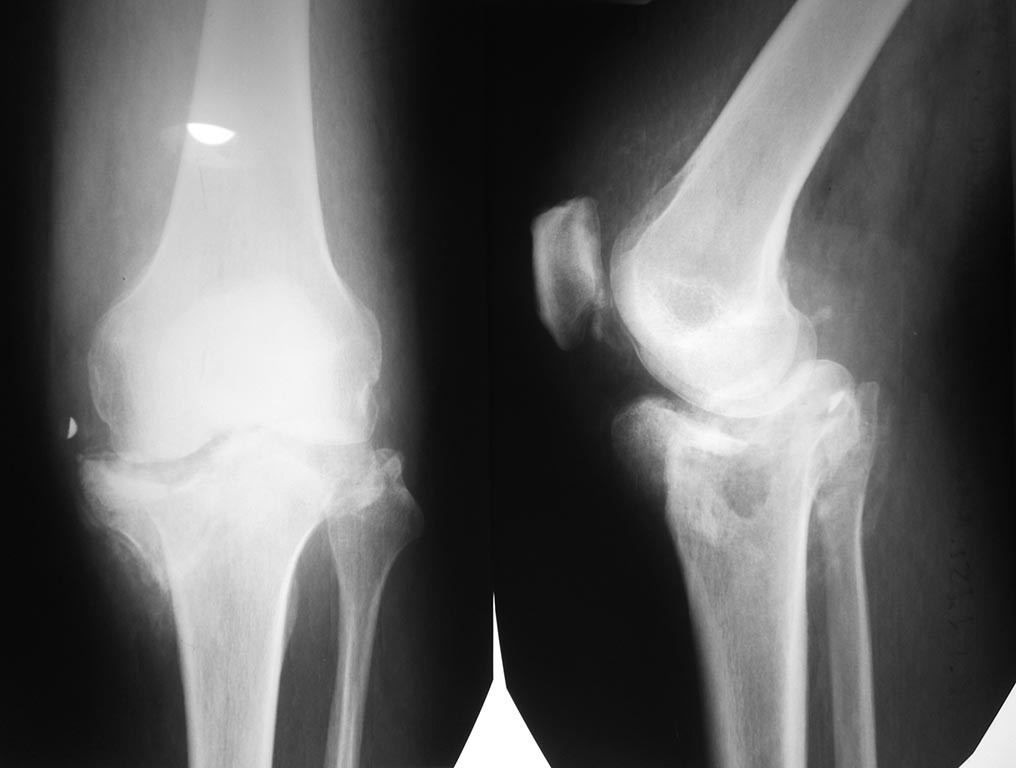

Рентгенограммы (1) январь 2015 год, (2) 25.05.2015 г.

Диагноз: Посттравматическая деформация проксимального отдела

большеберцовой кости как исход ее многооскольчатого (С3) перелома. По

срокам после травмы (более 6 мес): Ложный сустав (неоартроз)

проксимального отдела ББК. Эндопротез пациенту не доступен 100% (тем

более при таком дефекте ББК), поэтому мы можем предложить ему

остеосинтез или артродез.